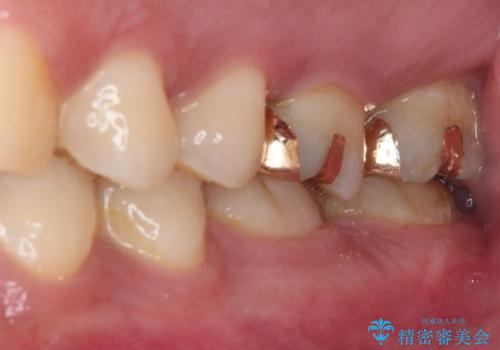

非常に咬合力が強く、銀歯やセラミックのような堅い素材では歯にダメージがかかり、治療を繰り返す可能性が高いと思われたので、ゴールドインレー(白金加金インレー、PGAインレー)にて、治療中の歯と銀歯が装着されている歯を修復治療することとしました。

ゴールドインレーは銀歯のインレーやセラミックインレーと比べ、「技工操作の精度が高く、適合が著しく良い」というメリットがあります。特に上の奥歯は歯科医師の操作が行いにくいため、「適合の良さ」は再治療のリスクを防ぐ上でとても重要な要素となります。

上の奥歯は金属色が見えることもないため、審美的な問題は全くありません。